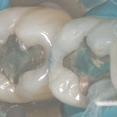

ancien amalgame

dépose des amalgames sous digue

nouveaux composites en place